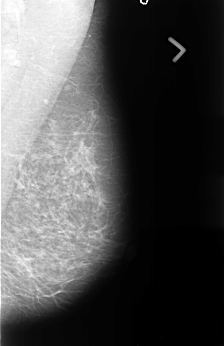

B_3441_1.RIGHT_CC

LEFT_CC LINES 4512 PIXELS_PER_LINE 2904 BITS_PER_PIXEL 12 RESOLUTION 50 NON_OVERLAY

FILE: B_3441_1.RIGHT_CC.OVERLAY

TOTAL_ABNORMALITIES 1

ABNORMALITY 1

LESION_TYPE CALCIFICATION TYPE PUNCTATE DISTRIBUTION CLUSTERED

LESION_TYPE MASS SHAPE IRREGULAR MARGINS OBSCURED-ILL_DEFINED

ASSESSMENT 3

SUBTLETY 2

PATHOLOGY MALIGNANT

TOTAL_OUTLINES 1

BOUNDARY